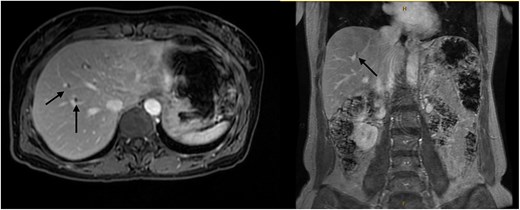

Six months after surveillance imaging, she was presented with ongoing abdominal pain. Liver function tests (LFTs) and Ca 19–9 remained normal at this time. A repeat abdominal US demonstrated an irregular gallbladder wall with thickening up to 5 mm and two stable gallbladder polyps, the largest measuring 7 × 8 mm (Fig. 2). Due to ongoing symptoms and changes on imaging, a laparoscopic cholecystectomy with intraoperative cholangiogram was performed without complication. At the time of surgery, the gallbladder was noted to have an area of wall thickening thought to be a Phrygian cap. The operative cholangiogram was consistent with PSC, with narrowed intrahepatic ducts observed (Fig. 3).

Preoperative ultrasound showing gallbladder polyp and wall thickening.